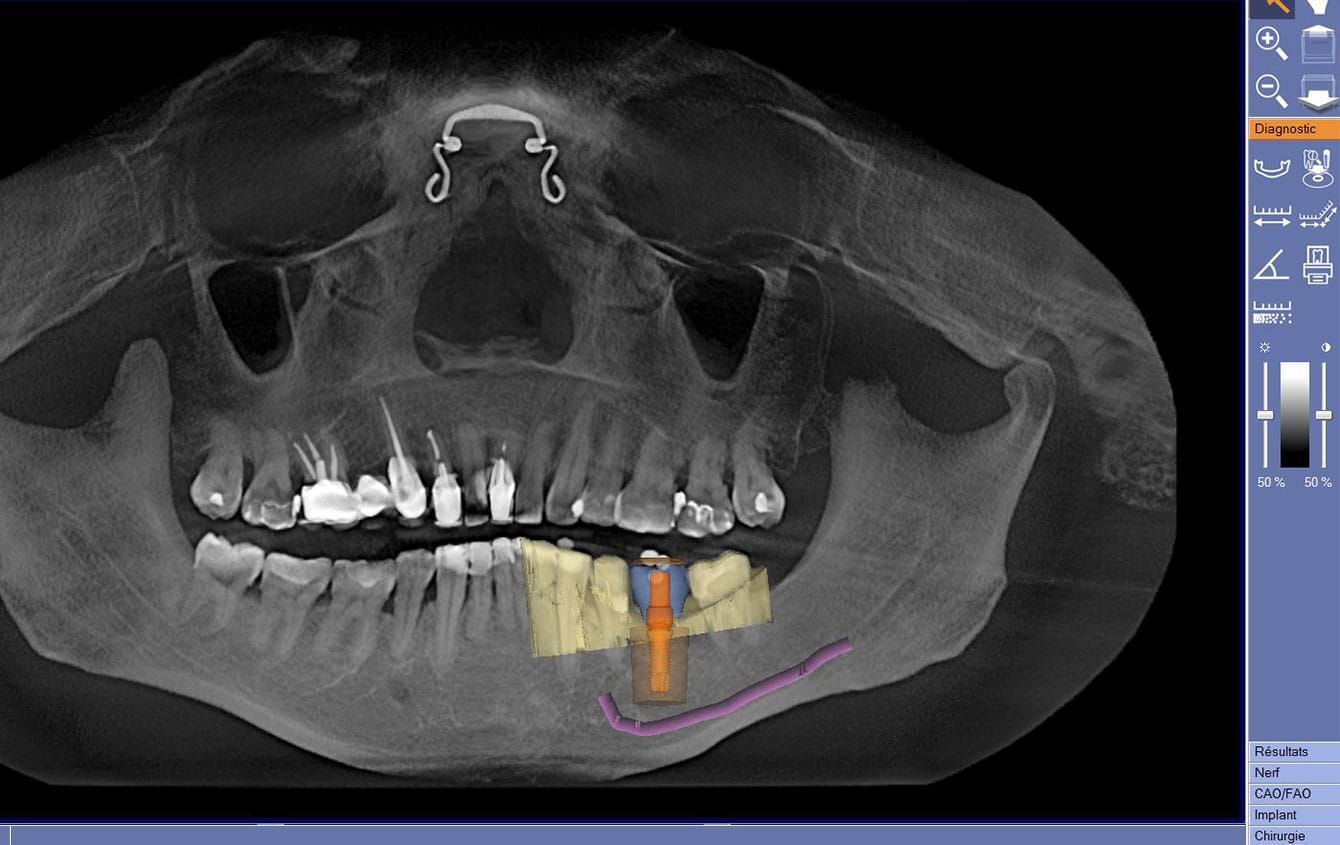

Le Cône Beam (CBCT)

C’est l’examen de choix pour la réalisation de la planification implantaire.

La planification implantaire

La planification implantaire consiste à déterminer le choix du nombre, de la longueur, du diamètre et de la position des implants, ainsi que leur orientation dans les différents plans de l’espace.

Grace au système CEREC, le projet prothétique supra-implantaire peut déjà être pris en compte. Cette planification axée sur la prothèse assure un positionnement optimal de l’implant avec le guide chirurgical CEREC GUIDE.

Dans ce cas clinique, la planification implantaire tient compte, pour la pose d’un implant localisé sur le site 36, du projet prothétique final (ici une couronne matérialisée en bleu).

Le nerf dentaire inférieur, élément noble à respecter dans cette chirurgie implantaire, est ici schématisé en violet.